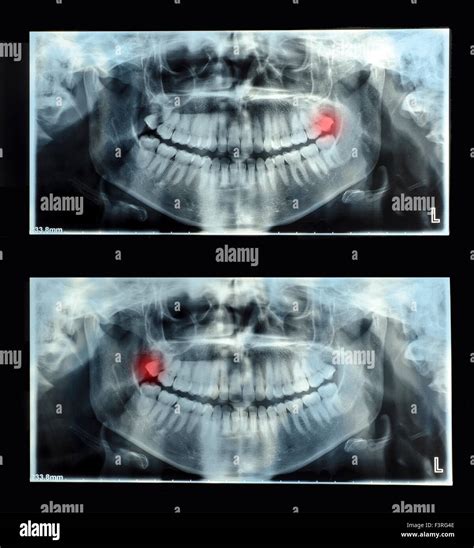

• Detecting Pathologies: Dentists can identify cysts, tumors, or infections within the jawbone that might be asymptomatic.

Once the images are generated, your dentist will examine them for any abnormalities. Because the image is an orthopantomogram, it flattens the curved jaw into a two-dimensional plane. This allows the dentist to compare the symmetry of the left and right sides of your mouth. They will look for:

• Signs of bone resorption or periodontal disease.